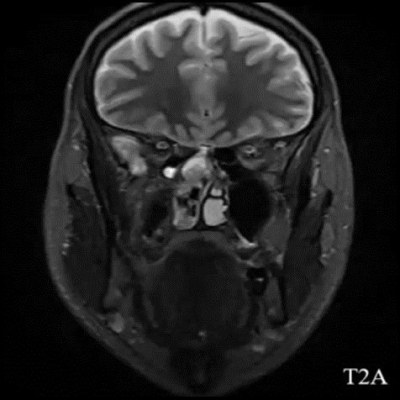

- A) Koronal T2A görntüde sağ süperior nazal kavite içerisinde hafif ekpansil karakterde, keskin sınırlı, nisbeten lobüle konturlu heterojen ara sinyal intensitye sahip yumşak doku lezyonu izleniyor (oklar).

- Estezionöroblastom görüntülemede tipik olarak nazal kavite tavanında, lamina cribrosa düzeyinden köken alan, etmoid sinüsler, orbita ve anterior kraniyal fossaya yayılım gösterebilen lobüle, agresif karakterli bir yumuşak doku kitlesi olarak izlenir ve sıklıkla komşu kemik yapılarda destrüksiyona neden olur. MR’da lezyon genellikle T1-ağırlıklı serilerde izo/hipointens, T2-ağırlıklı serilerde hiperintens sinyal özelliği gösterir ve kontrast sonrası heterojen güçlü kontrastlanma izlenir. İntrakraniyal uzanım varlığında tümör ile frontal lob parankimi arasında izlenen peritümöral periferik kistik değişiklikler, estezionöroblastom için literatürde tanımlanmış ayırt edici ve spesifik bir MR bulgusudur.